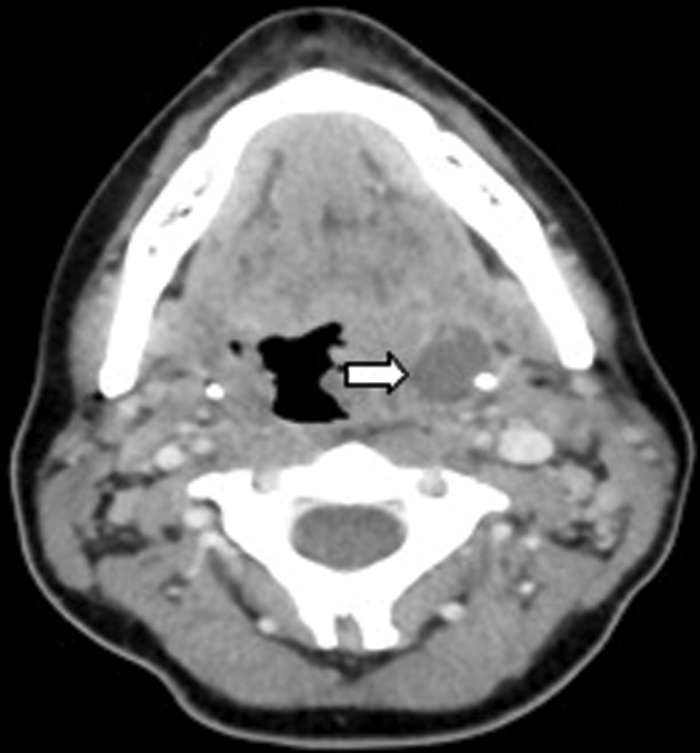

Clinical examination excluded a dental cause, as the patient was edentulous, however an ultrasound demonstrated an abscess over the right masseter muscle. Figure 3 shows an abscess collection in the right buccal space. Figure 4 demonstrates the cause of the abscess (and otalgia) - a tooth root buried underneath the gingiva, with associated buccal bone perforation.

Figure 3: Contrast enhanced soft tissue axial CT demonstrating a buccal space abscess (white arrow).